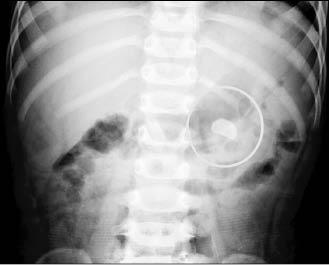

高雄一名1歲10月大幼兒患有先天巨大輸尿管,長期尿流不順,且家人每天三餐餵食鈣粉,希望他長得高又壯,沒想到反而補過頭,尿鈣沈澱、結晶,左腎出現1.5公分的結石,經泌尿科醫師以體外震波碎石術,才把結石擊碎、排出。

這名幼兒在胎兒時期、媽媽懷孕產檢時,就發現他的左腎有輕微水腫,出生後,持續接受追蹤檢查。1歲時發現,左腎有不明鈣化點,追蹤半年多,鈣化點形成具體的結石。

高長震波碎石護理師高儷芳說,小病人體外震波碎石,需要很小心,怕他亂動,得全身麻醉。也因為年紀小,結石形成時間不久、硬度不大,經體外震波擊中後,呈粉碎剝落,隔天X光檢查,石頭碎片隨著輸尿管順利排出。